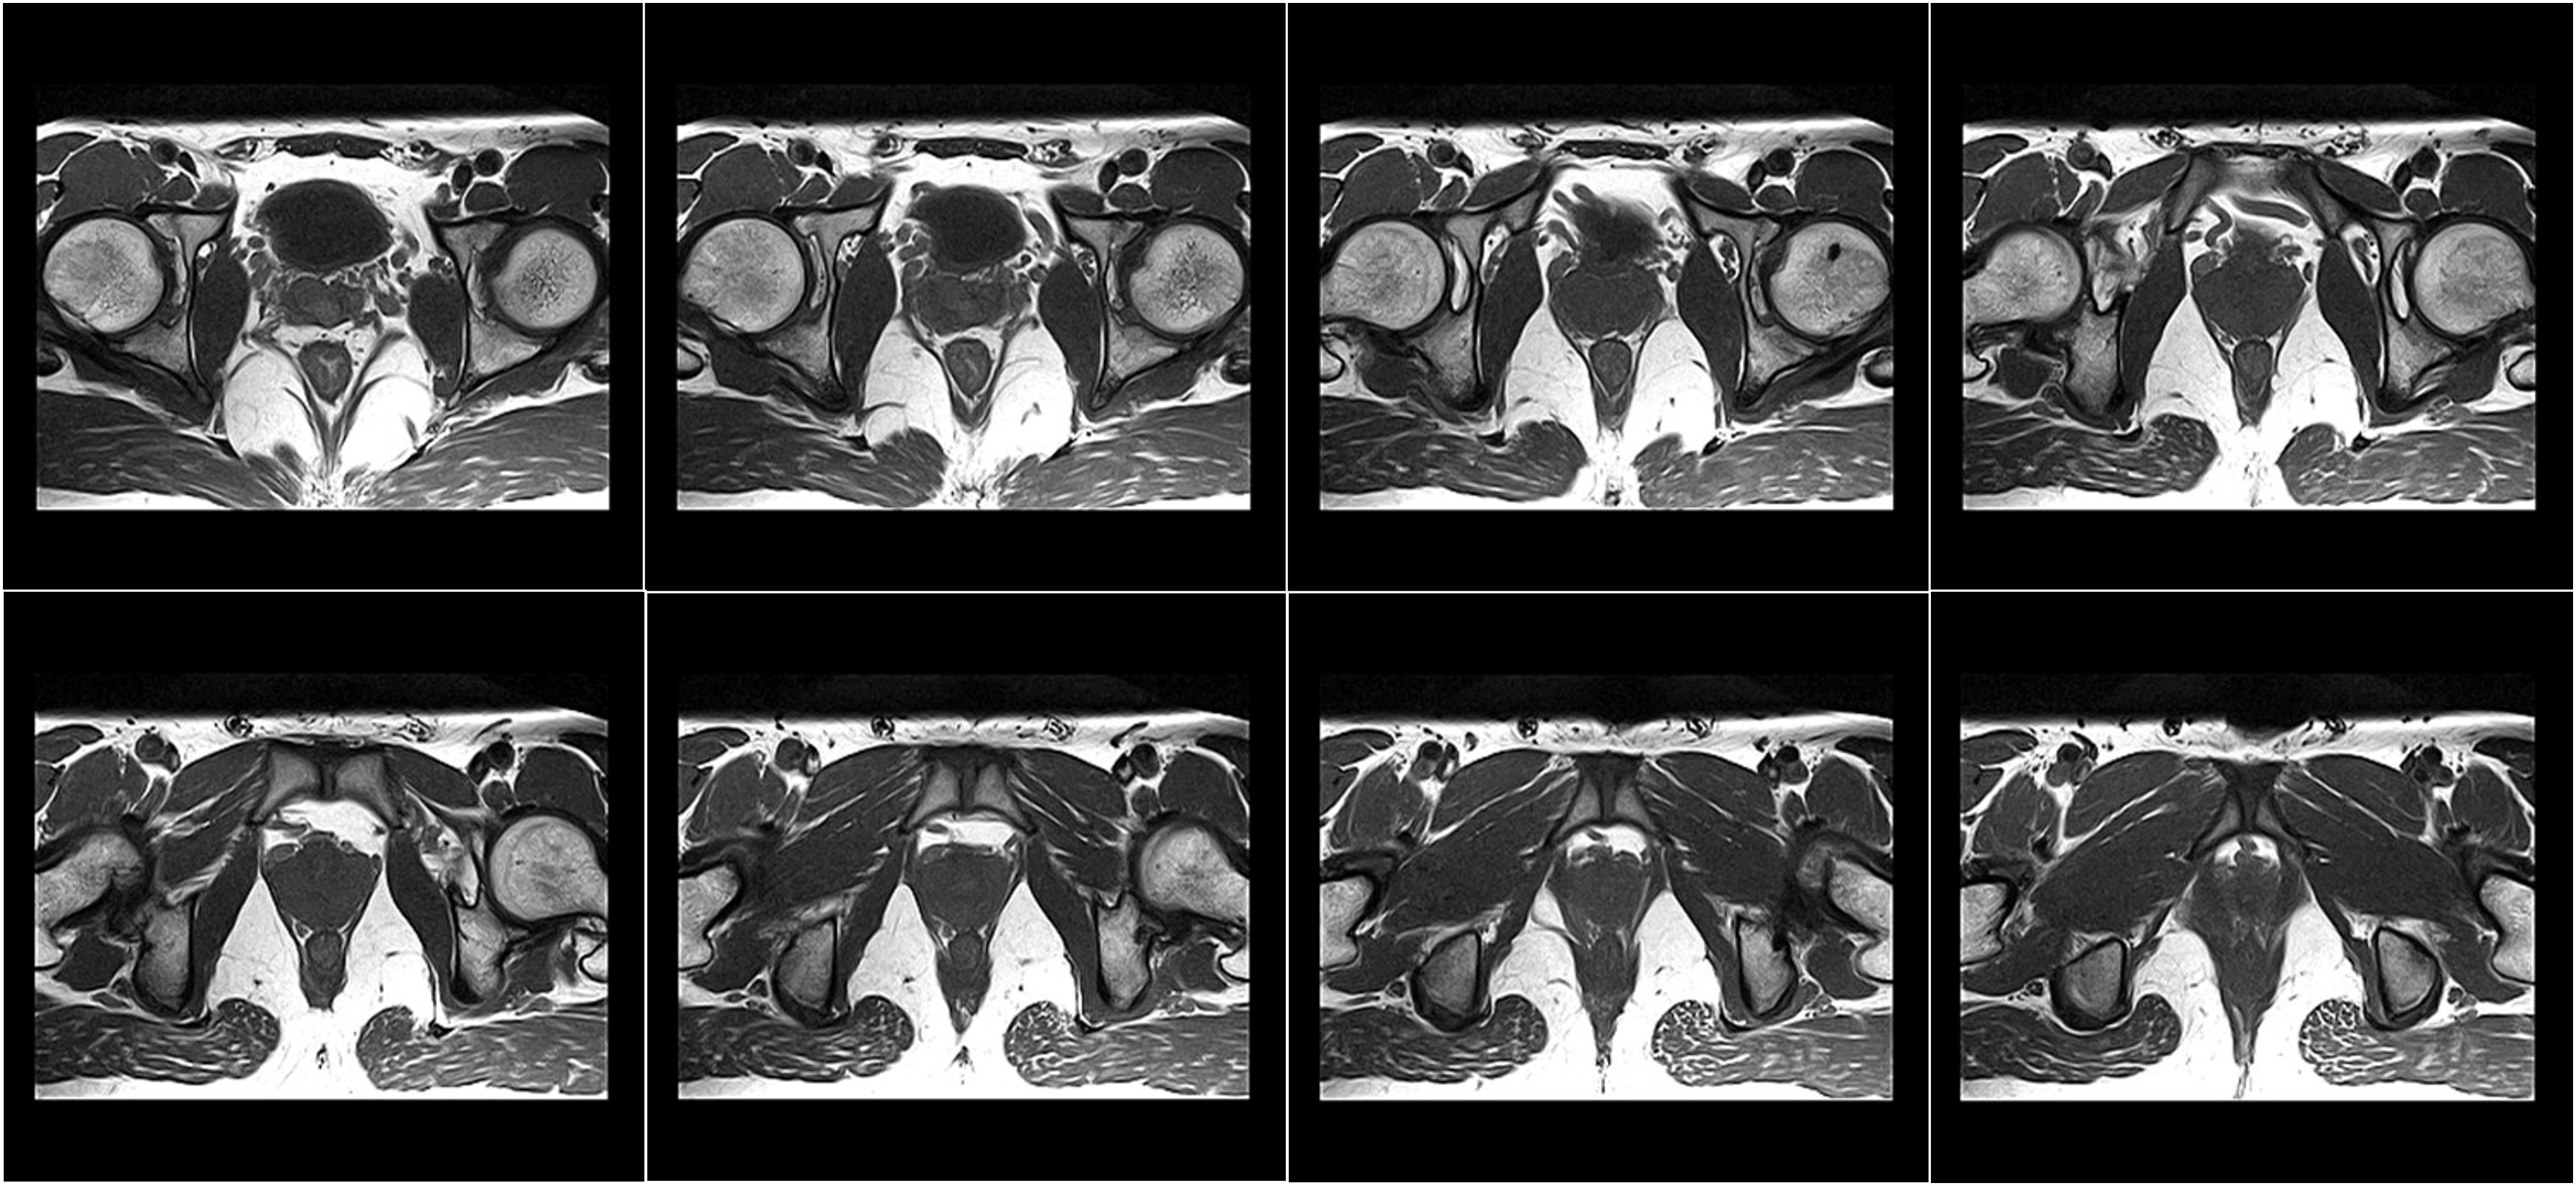

Hình ảnh lâm sàng